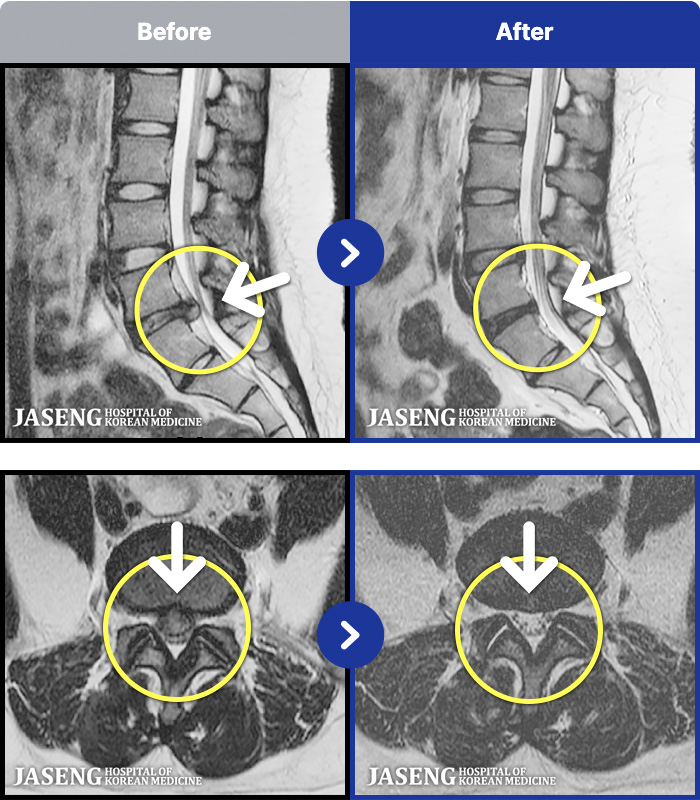

MRI ġ

1,299 MRI ũ ʸ Ȯϼ.